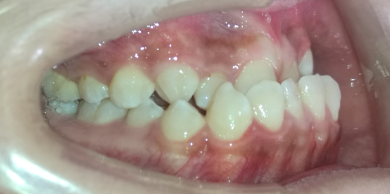

病例1

治疗前